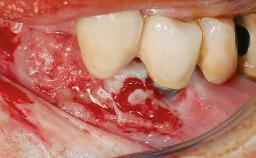

A 65-year-old female patient was referred to the periodontist for assessment and management of implant site 12. Implant 12 had been placed ten years previously and restored with a cemented single crown. The patient was a non-smoker in good general and periodontal health. On examination there were 7 mm probing depths at implant 12 with suppuration and bleeding on probing. The patient was aware of the presence of pus but had no discomfort. A periapical radiograph showed marginal bone loss to approximately the third thread of the implant. Previous radiographs obtained from the referring clinician indicated that there had been progressive bone loss since the implant was restored. A diagnosis of periimplantitis was made.